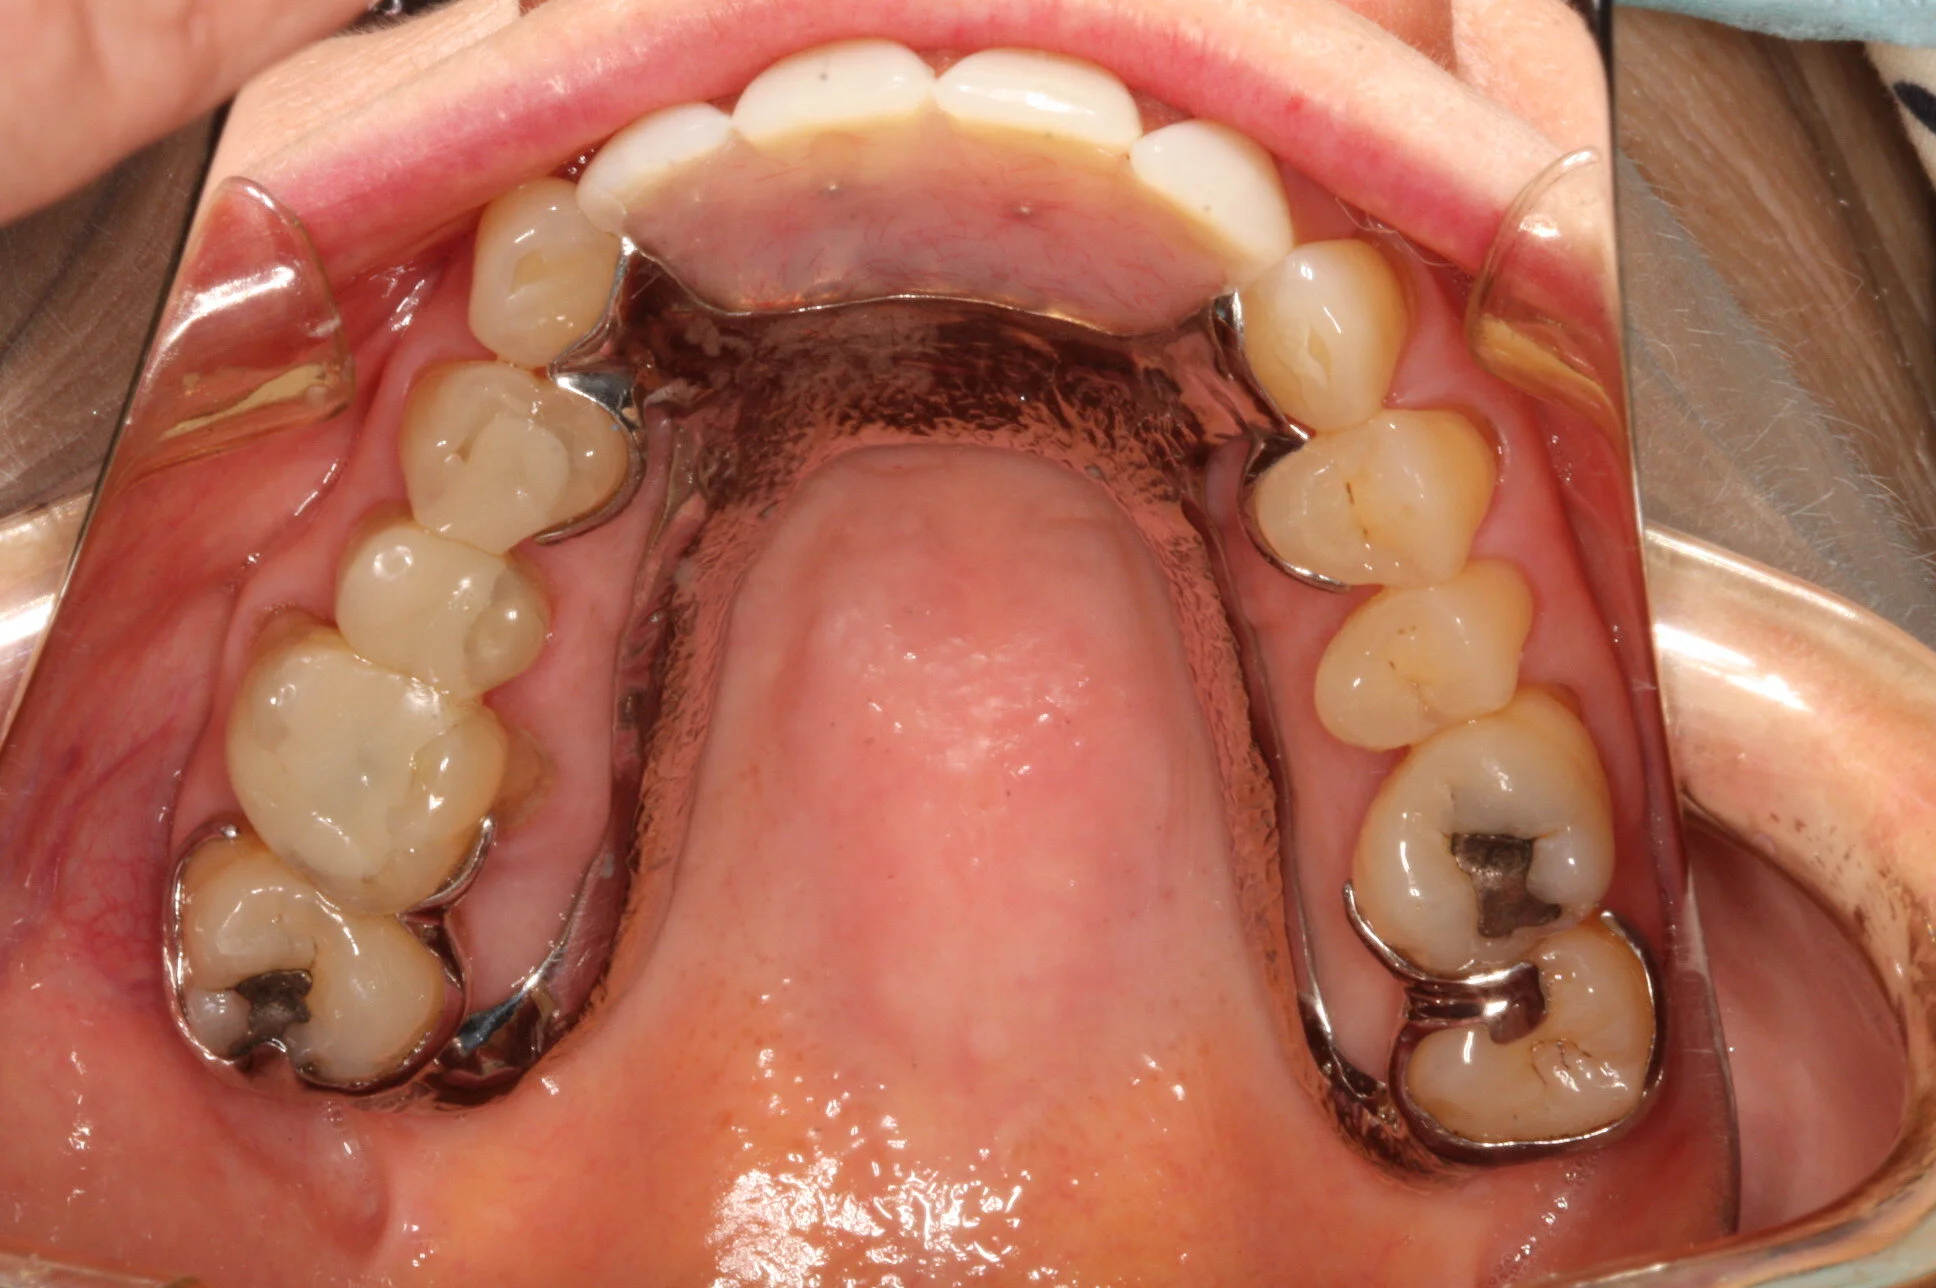

Dentists are seeing an increase in patient edentulism in their practices. A well-designed partial removable dental prosthesis of high quality improves patients’ smiles, chewing and speech function. This treatment modality is often a valid alternative to fixed dental prostheses supported by teeth or implants. In many complete edentulous scenarios, a removable denture stabilised and retained by implants is a preferred outcome compared with implant fixed prostheses. Diagnosis, planning decisions, treatment procedures and clear maintenance protocols are the keys to success in removable prosthodontics.

• Integrating fixed and removable prostheses

• Mucosal- and implant-borne removable prostheses